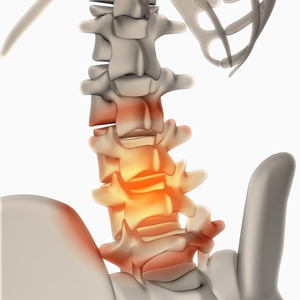

Hernia Discal Lumbar y Cervical

La hernia discal puede comprimir raíces nerviosas generando dolor intenso, hormigueo o debilidad en brazos o piernas. Nuestro enfoque combina ajustes quiroprácticos suaves, terapia física descompresiva y rehabilitación para reducir presión y promover regeneración natural del disco.

- Dolor irradiado a glúteos, piernas o brazos

- Adormecimiento o pinchazos

- Dificultad para estar sentado mucho tiempo

Dolor de Espalda y Lumbalgia Crónica o Aguda

La lumbalgia es una de las consultas más frecuentes. Puede originarse en sobrecarga muscular, mala biomecánica o alteraciones vertebrales. Aplicamos corrección estructural + fortalecimiento específico para resultados duraderos sin depender de medicamentos.

- Rigidez matutina

- Dolor al inclinarse o levantar peso

- Limitación en movimientos cotidianos

Ciática y Dolor del Nervio Ciático

La irritación o compresión del nervio ciático genera dolor punzante que baja por la pierna. Identificamos la causa raíz (hernia, piriforme, estenosis) y usamos técnicas descompresivas + movilización neural para aliviar rápidamente y prevenir recaídas.

- Dolor eléctrico desde glúteo a pie

- Debilidad o hormigueo en pierna

- Empeora al sentarse o toser